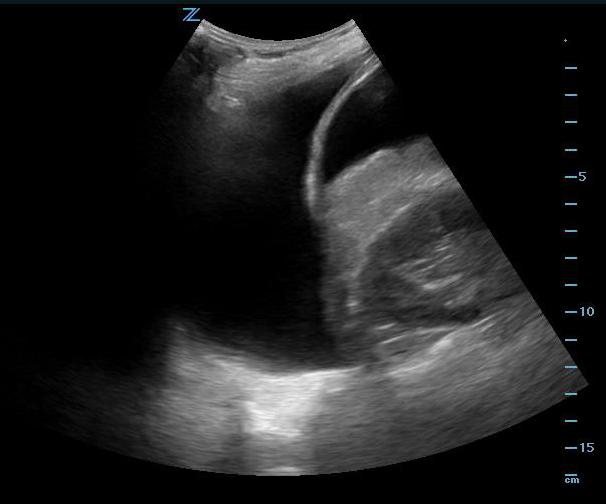

- Left Coronal and Intercostal Oblique Views:

- This is often the most difficult abdominal view to obtain. Place the probe in the posterior-axillary line at about the 6th to 9th intercostal space with the transducer indicator pointed cephalad, producing a coronal view. From this position the interface between the spleen and left kidney can be found.

- Free fluid is rarely seen between the spleen and the kidney but rather surrounding all other parts of the spleen or between spleen and diaphragm.

- To get rid of rib shadows, and to get a better view of the spleen, slide the probe cephalad and rotate it very slightly clockwise with the indicator pointing toward the posterior axilla, producing an intercostal oblique view, so that the spleen (not the kidney) is seen (Figure 13 shows the probe position). This view will allow good images of the lower tip and superior surface of the spleen, where intraperitoneal free fluid is most likely to collect. The diaphragm will also be seen in this view, just superior to the spleen.

- A pleural effusion will appear as a jet black stripe or triangle just superior to the diaphragm. (Video 10)